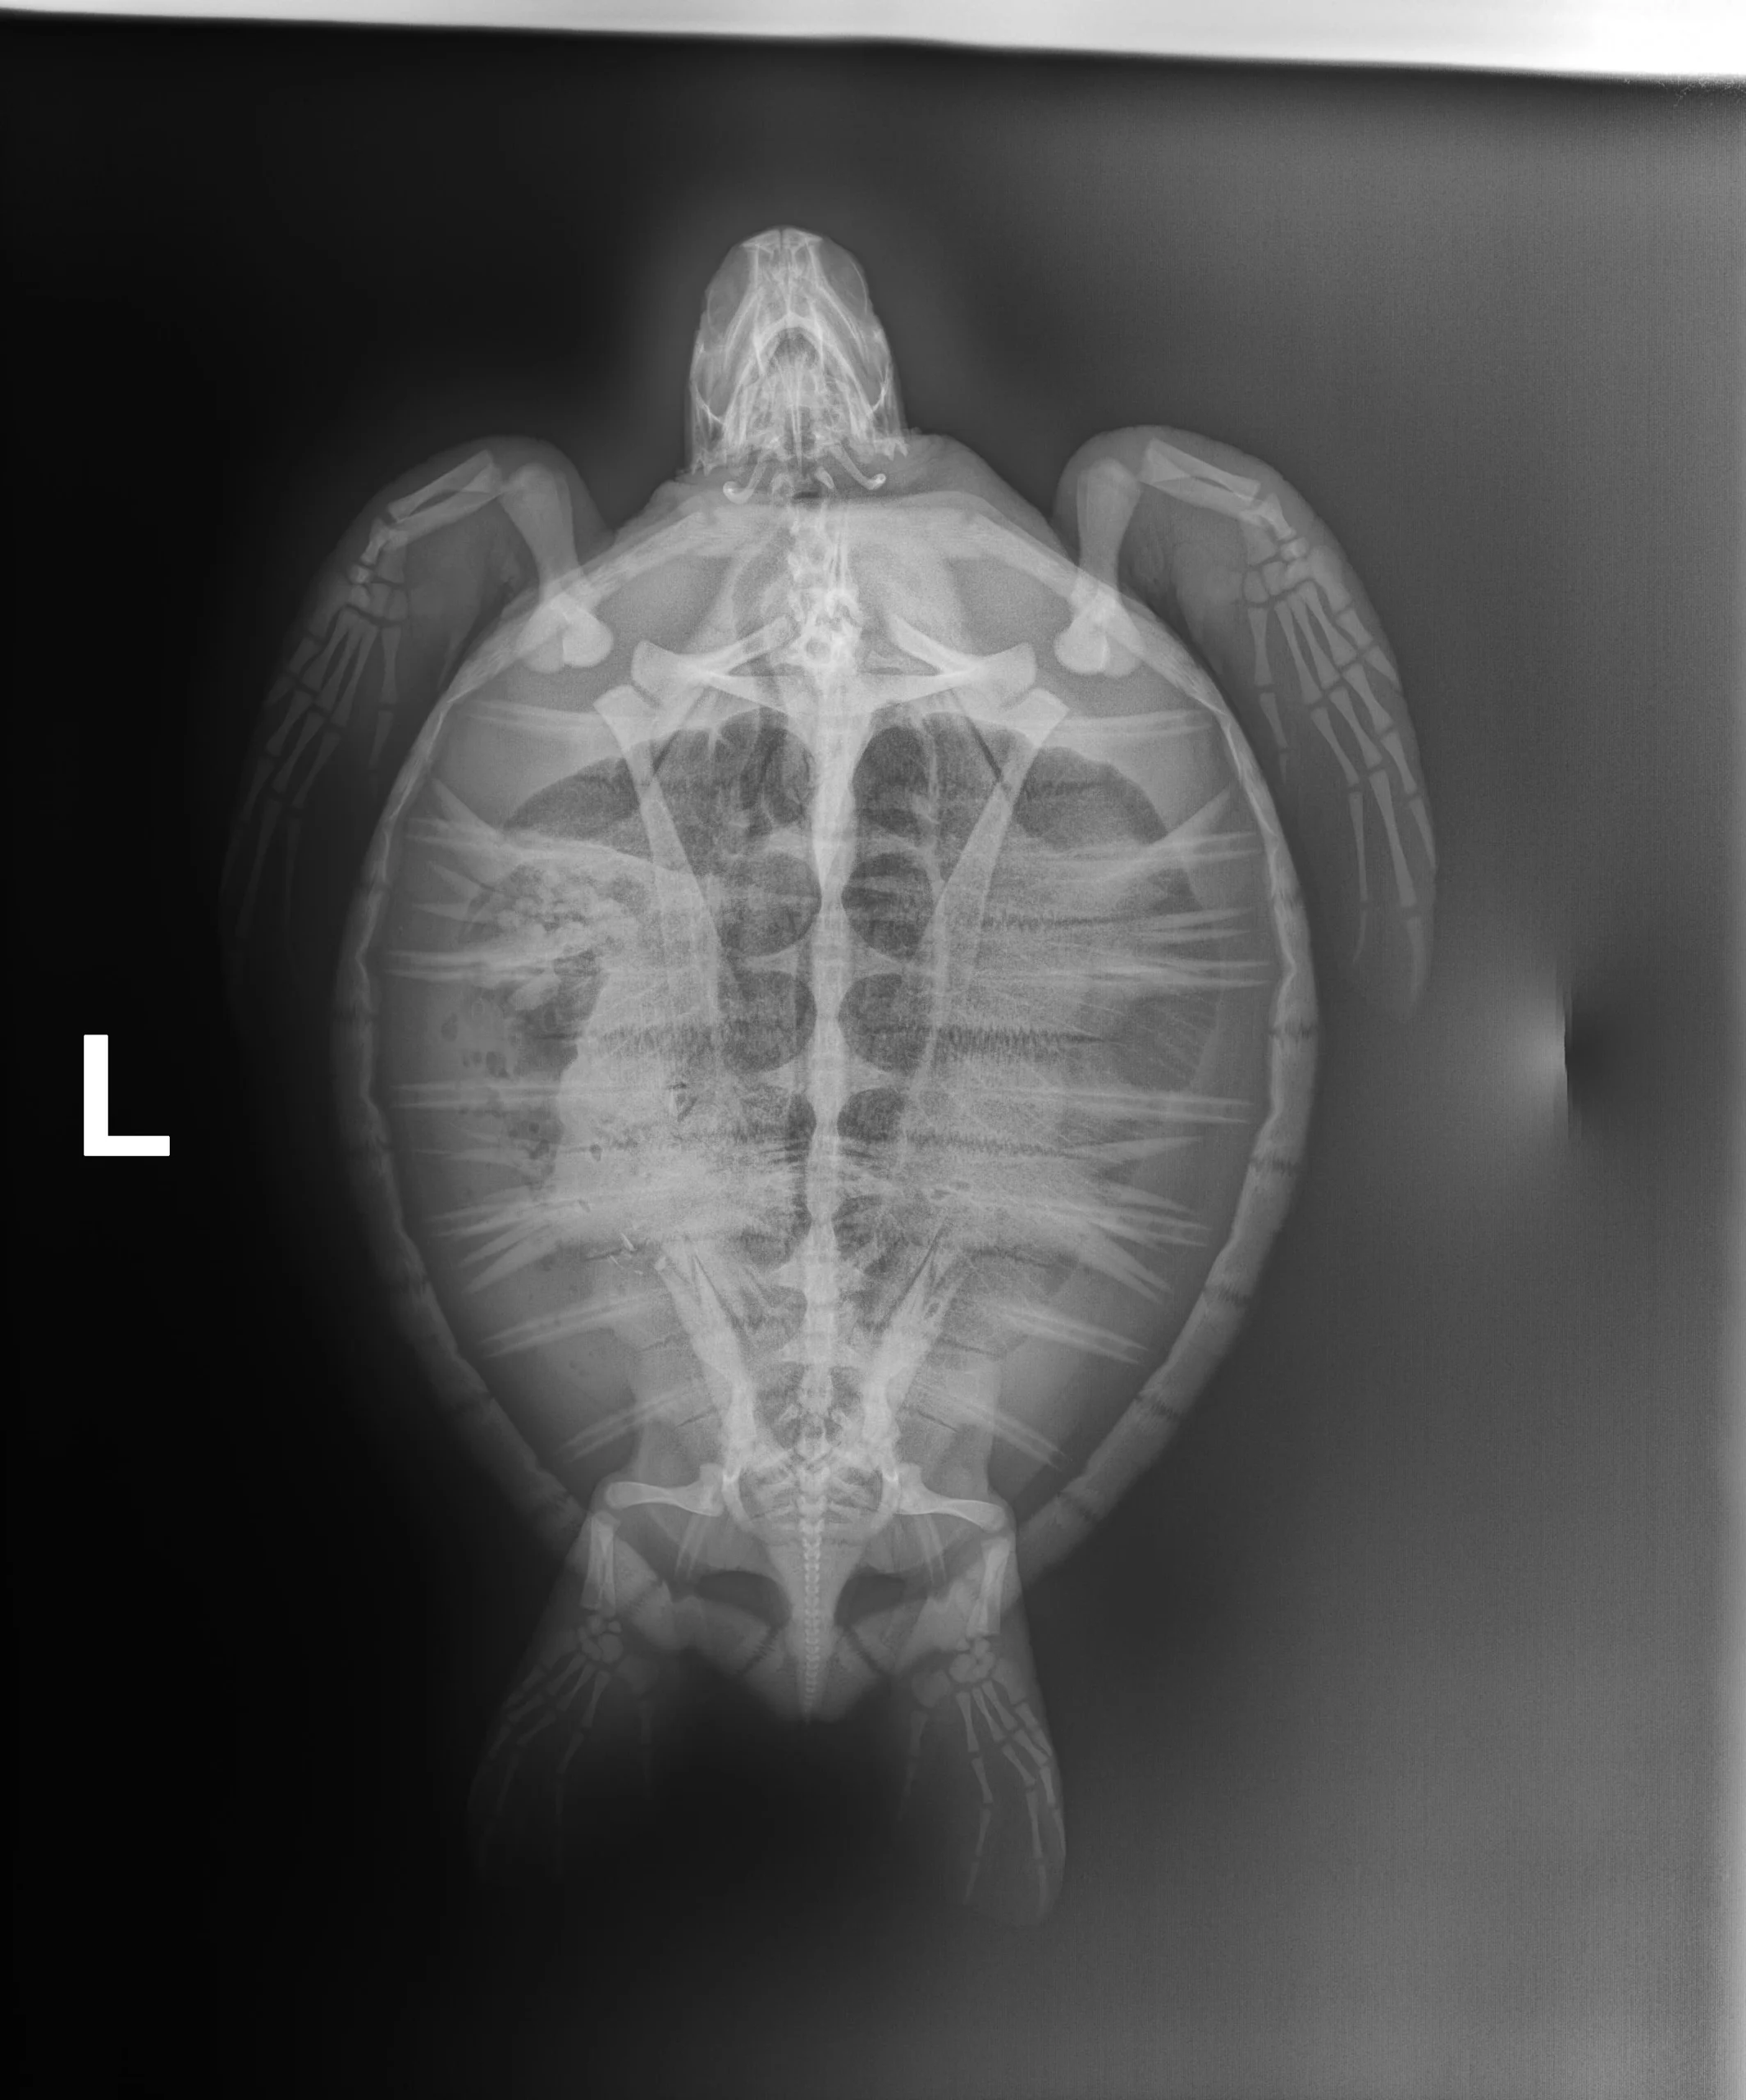

3.40lbs non-FP juvenile green

Moderate plastron and carapace abrasions, abrasions on all four flippers, small abrasion on the head